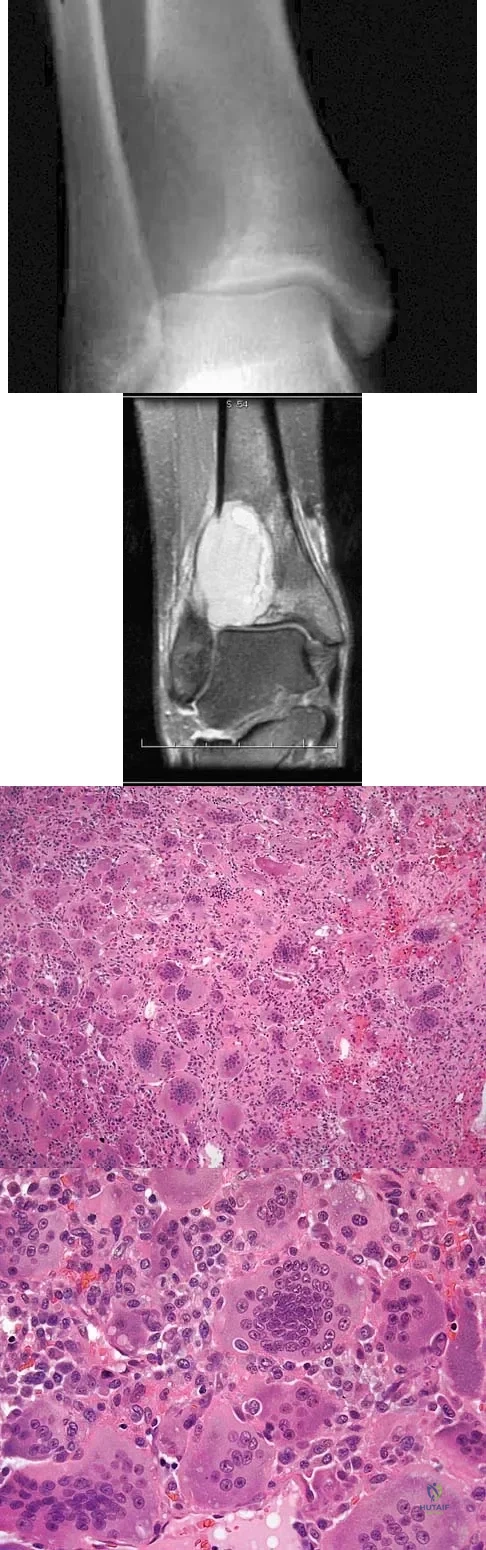

A 19-year-old girl has had pain and swelling in the right ankle for the past 4 months. She denies any history of trauma. Examination reveals a small soft-tissue mass over the anterior aspect of the ankle and slight pain with range of motion of the ankle joint. The examination is otherwise unremarkable. A radiograph and MRI scan are shown in Figures 45a and 45b, and biopsy specimens are shown in Figures 45c and 45d. What is the most likely diagnosis?

A 54-year-old woman reports worsening pain in her buttock, especially when sitting for long periods of time. She has occasional pain and paresthesias radiating down her posterior leg. She has no significant medical history. MRI scans are shown in Figures 15a and 15b and a biopsy specimen is shown in Figure 15c. What is the most likely diagnosis?

A 38-year-old man has an enlarging left paraspinal soft-tissue mass. Based on the MRI scans and biopsy specimens shown in Figures 32a through 32e, what is the most likely diagnosis?